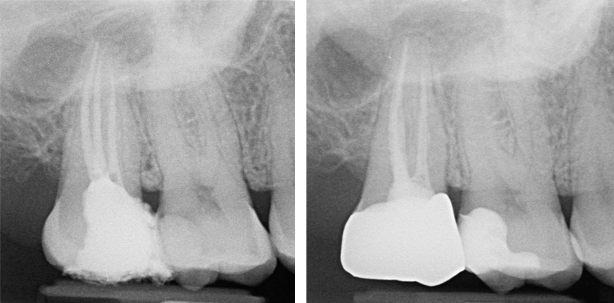

Der Patient konsultierte die Praxis und klagte über intermittierend auftretende Schmerzen am Zahn 35 (Abb. 5). Klinisch präsentierte sich der Zahn als perkussionsempfindlich. Der Zahn diente als distaler Brückenpfeiler. Unter Lokalanästhesie wurde die Brücke entnommen und es offenbarte sich eine ausgeprägte Sekundärkaries, die vollumfänglich exkaviert worden ist. Allerdings hatte die Karies bereits das Pulpengewebe erreicht. Um den Zahn zu erhalten und in die implantatprothetische Restauration einzubinden, entschieden wir uns nach einer Beratung mit dem Patienten für eine endodontische Behandlung.

Nach dem Anlegen der Trepanationsöffnung wurden die Kanaleingänge lokalisiert. Die Trepanationsöffnung sollte hierbei so klein wie möglich gehalten werden, um den betroffenen Zahn nicht zu schwächen. Ein geradliniger Zugang wird für die maschinelle Aufbereitung empfohlen. Zur Bestimmung der Arbeitslänge diente die obligate Röntgenmessaufnahme (Abb. 6). Um eine Elimination von Mikroorganismen aus dem Wurzelkanalsystem sowie die Auflösung von Pulparesten, nekrotischem Gewebe, Dentinspänen etc. zu erreichen, wurde Spülflüssigkeit in die Kavität eingebracht.

Für die adäquate Versorgung des Kanals bevorzugen wir die kalte Obturationstechnik mit RECIPROC-Guttaperchastiften. Nach dem Trockenlegen des Kanals mit der passenden Papierspitze (RECIPROC) wird der Stift mit einem Sealer benetzt und in den Kanal eingebracht. Nach abschließender Kontrolle der Wurzelkanalfüllung konnte die Trepanationsöffnung mit einem adhäsiven Material verschlossen werden (Abb. 7). Für die festsitzende prothetische Versorgung der Freiendlücke wurde der implantatprothetische Weg gewählt und der Zahn 35 in die Restauration eingebunden. Der Zahn fungierte als wertvoller Pfeiler, was aufgrund des für die Implantate relativ geringen Knochenangebots zusätzlich Sicherheit für den Langzeiterfolg bot. Elf Monate später erfolgte eine Nachkontrolle (Abb. 8). Sowohl die endodontische Versorgung des Zahns 36 als auch die Implantattherapie können als erfolgreich bewertet werden.